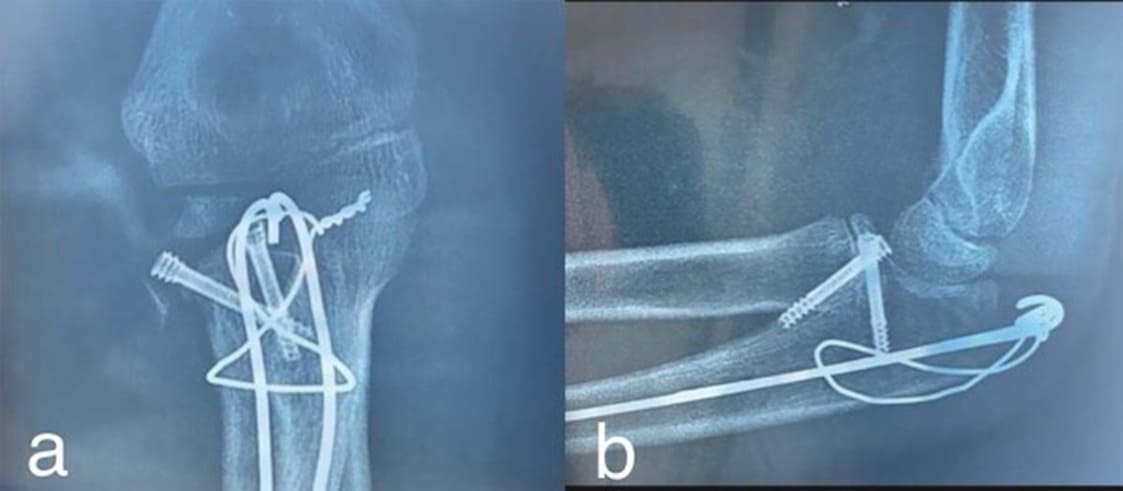

Figure 4: Anatomical reduction of fractures and fixation of the coronoid fracture with two Herbert screws and the metaphysical olecranon fracture with a figure-of-eight wire

Figure 5: Intraoperatively, the radial head stability was checked; the annular ligament was normal, and the radial head was stable in flexion-extension and pronation- supination.